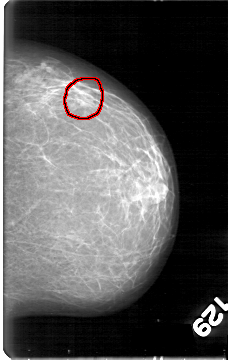

D_4045_1.LEFT_CC

LEFT_CC LINES 5386 PIXELS_PER_LINE 3406 BITS_PER_PIXEL 12 RESOLUTION 43.5 OVERLAY

FILE: D_4045_1.LEFT_CC.OVERLAY

TOTAL_ABNORMALITIES 1

ABNORMALITY 1

LESION_TYPE MASS SHAPE LOBULATED MARGINS OBSCURED

ASSESSMENT 0

SUBTLETY 3

PATHOLOGY BENIGN

TOTAL_OUTLINES 2

BOUNDARY